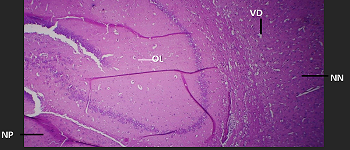

Exploring the Effects of Byrophyllum Pinnatum Extract on the Cerebrum of Adult Wistar Rats

View Submission